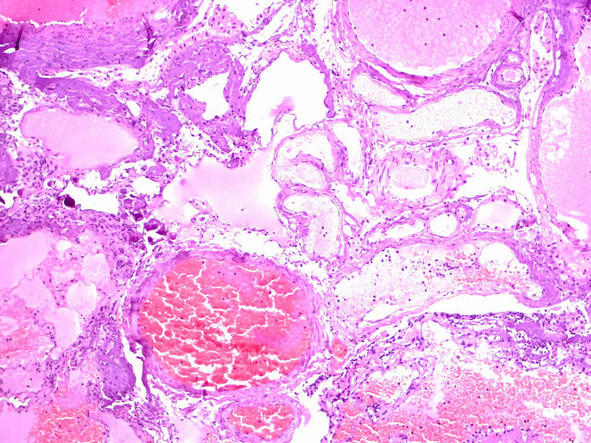

При рутинном исследовании в световом микроскопе (срезы толщиной 5 мкм, окраска гематоксилином и эозином, при необходимости – докрашивание по Ван-Гизон и Маллори) каверномы представляют собой конгломерат тонкостенных полостей разнообразной неправильной формы, выстланных эндотелием и разделенных соединительнотканными перегородками. Соединительная ткань перегородок может быть представлена как тонкими коллагеновыми волокнами, так и грубоволокнистой фиброзной тканью с различной степенью дистрофических изменений. Характерным признаком является отсутствие в стенах каверн гладкомышечных клеток и эластических волокон, а также мозговой ткани между кавернами (рис. 11) (2, 236, 299, 333).

Лишь в отдельных препаратах можно обнаружить незначительные прослойки мозговой ткани. Реактивно измененная мозговая ткань может быть также выявлена вокруг каверн, полностью отделенных, «отшнурованных», от основного конгломерата (рис. 12).

Полости, образующие каверному, могут быть заполнены жидкой кровью либо тромбами в различной стадии формирования (рис. 13).

Довольно часто в строме встречаются признаки повторных кровоизлияний в виде остатков гематом различной давности. По периферии каверномы часто можно обнаружить фрагменты капсулы, типичной для хронической гематомы (рис. 15).

Рис. 11. Кавернозная мальформация «классического» типа —конгломерат сосудистых полостей различной формы и размеров, выполненных кровью.Ув. х 100

Рис. 13. Тромбоз и склероз сосудистых полостей в «классической» кавернозной мальформации.Ув. х 200

Рис. 14. Кальцификат (стрелка) и склеротические изменения в стенках сосудистых полостей. Ув. х 100

Рис. 15. А. Начальная стадия формирования стенки гематомы – скопления макрофагов, нагруженных гемосидерином. Ув. х 400. Б. Сформировавшаяся капсула гематомыс отложениями гемосидерина, лимфоплазмоцитарной инфильтрацией и новообразованными сосудами. Ув. х 200